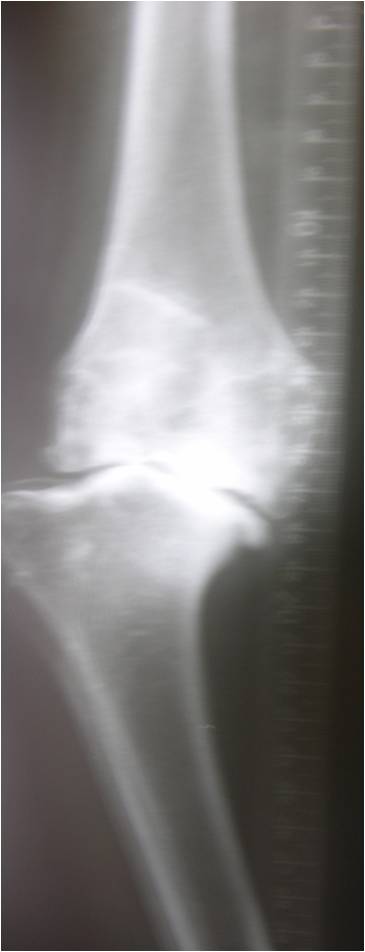

This is an Xray of a 53 year old lady with history of septic arthritis when 15 years of age send for opinion by a good friend of mine.

This is the closet to a ball and socket knee joint. The only similar case I did was a 83 year old lady from Delhi wherein we did a Link RHK( Pic below). The preop pics was with valgus correction for templatingThere was no endpoint in Varus valgus under anaesthesia and the femur appeared to drop off the tibia. In view of her age we did RHK. Its 3 years now and so far successful

Here the h/o septic arthritis which is hopefully quiscent now. In view of her one could try to use a femoral metephyseal sleeve TM may be and a Varus valgus contrained knee. AN RHK should be on table in case one tries a VV constained knee. The baja patella is the next problem if resurfaced put a smaller button superiorly. Any other comments are welcome